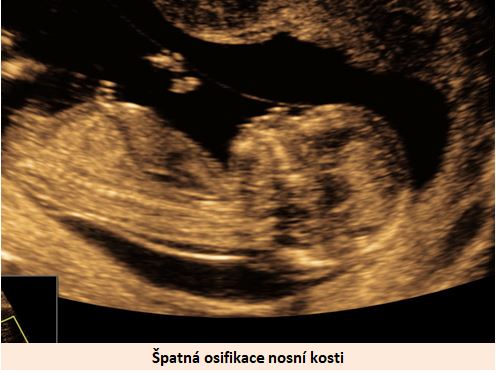

Ultrazvuková diagnostika se při screeningu v 1. trimestru opírá o šířku podkoží v záhlaví plodu, osifikaci nosní kůstky a nálezu abnormálních průtoků v srdci plodu (trikuspidální regurgitace, reversní tok v ductus venosus).

Pracoviště se zkušenostmi v prenatální diagnostice a s dobrým přístrojovým vybavením je schopno vyslovit podezření na tento syndrom ve více jak 90% případů již při ultrazvukovém vyšetření ve 12-13. týdnu těhotenství. .